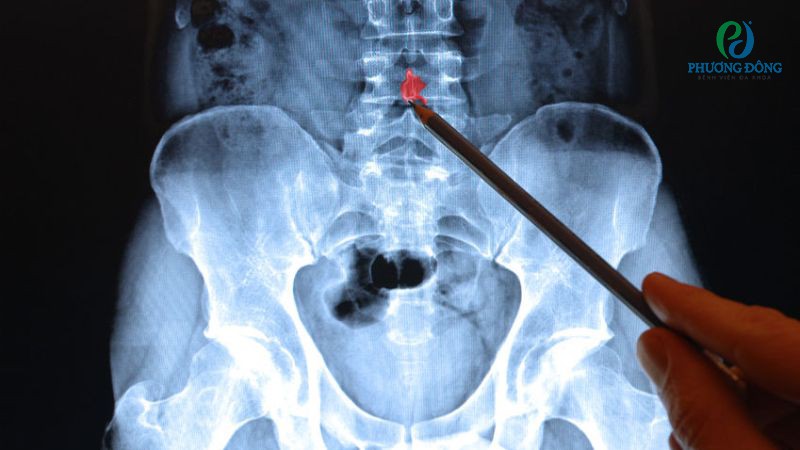

Theo tiêu chuẩn Meyerding, trượt đốt sống được chia thành 5 mức độ dựa trên phim X-quang tư thế nghiêng. Cụ thể:

- Độ 1: Đốt sống trượt ra trước từ 0 - 25% so với thân đốt sống dưới.

- Độ 2: Đốt sống trượt ra trước từ 25 - 50%.

- Độ 3: Đốt sống trượt ra trước từ 50 - 75%.

- Độ 4: Đốt sống trượt ra trước từ 75 - 100%.

- Độ 5: Đốt sống phía trên trượt hoàn toàn, tách rời khỏi thân đốt sống dưới.

Phân độ tình trạng đốt xương sống bị trượt

- Chụp X-quang tư thế thẳng, nghiêng, cúi tối đa, ưỡn tối đa giúp xác định vị trí cùng tỷ lệ trượt.